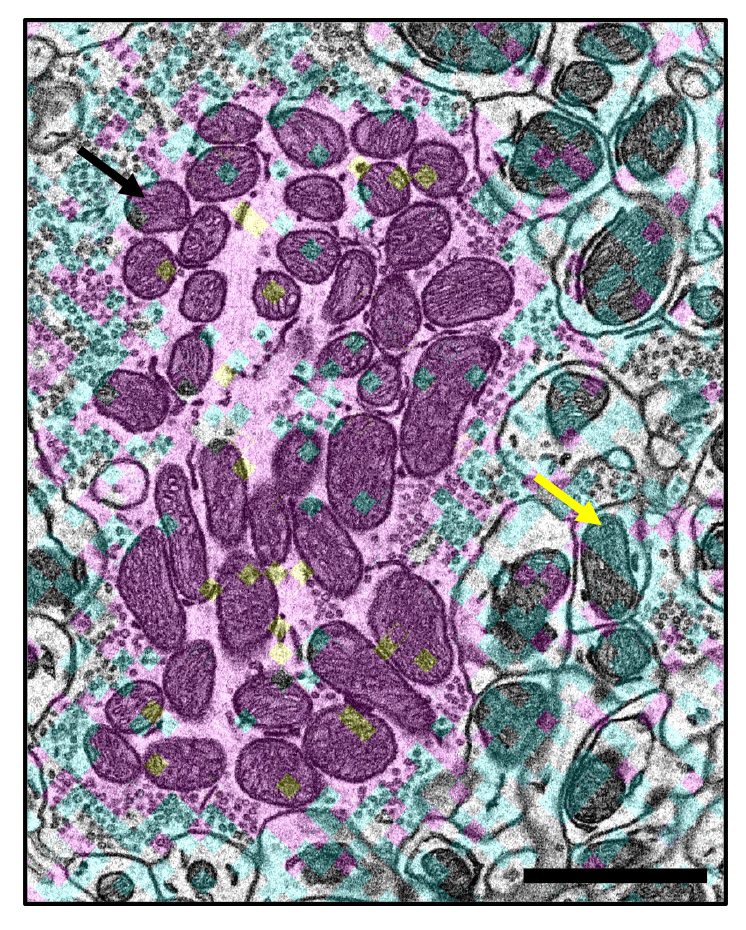

Миоглобин, это специализированное белковое соединение, которое содержится в мышечных клетках․ Его основная функция — связывать молекулы кислорода и доставлять их к митохондриям, где кислород участвует в процессе выработки энергии․ Представьте себе мост между атмосферой и внутренностью клетки — именно этой функцией обладает миоглобин․ Благодаря ему мышцы могут продолжать работу и восстановление даже при временном снижении поступления кислорода из крови․

На этом этапе важную роль играет миоглобин: он захватывает кислород из разряженной среды капилляров и удерживает его, создавая депо внутри мышцы․ Это обеспечивает постоянное снабжение кислородом даже в моменты, когда кровоток немного замедляется или возникает потребность во внезапной энергии․ Таким образом, диффузия кислорода происходит не только между кровью и мышцами, но и внутри самой мышцы с помощью миоглобина․

Диффузия кислорода обеспечивает не просто доставку кислорода, а его равномерное распределение по всему объему мышцы и поддержание работы митохондрий․ Миоглобин служит своего рода "топливным запасом", позволяющим мышечной ткани функционировать даже при временной остановке кровотока или использовании кислорода мышцами во время физических нагрузок․

Миоглобин действует как резервуар кислорода, который доступен мышцам в критические моменты, например, при сильной физической нагрузке или недостатке кислорода в крови․ В процессе работы мышц кислород, связанный с миоглобином, поступает в митохондрии, где он участвует в окислительном фосфорилировании — способе выработки АТФ, основного источника энергии для клеток․